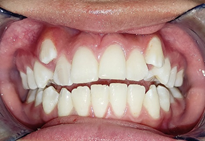

Al analizar las fotografías intraorales revelaron lo siguiente (Figura 2): Fotografía frontal: líneas medias dentales no coincidentes la inferior se encuentra con una desviación de 2 mm hacia la derecha, mordida abierta y caninos superiores ectópicos. (A). Fotografía lateral derecha (B) e izquierda (C): Clase II molar, clase canina no aplica debido a que los caninos no se encuentran en el arco.

Fotografía oclusal superior: Forma de arcada ovoide, apiñamiento en el sector anterior, palatinización de las piezas 1.2 y 2.2, piezas 1.3 y 2.3 ectópicas, paladar profundo (D). Fotografía oclusal inferior: Forma de arcada oval, lingualización de las piezas 4.5 y 4.6, ausencia de la pieza 3.7 (E). Fotografía de resalte: La sobremordida horizontal y vertical de -2 mm (F).